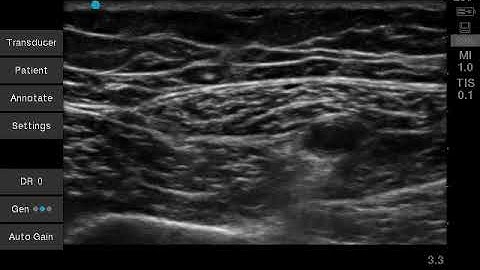

Adductor Canal Block - Does Nerve to Vastus Medialis Have To Be SEPARATELY Targeted?